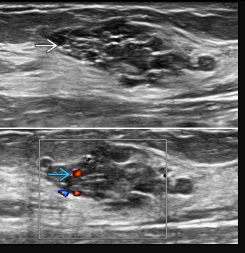

The affected side (left side here) show diffuse, relatively ill-defined, echogenic breast fat tissue and increased colour flow Doppler, and enlarged lymph nodes in the axilla, with no evidence of focal skin thickening or traction, well-defined mass, or nearby extra-breast tissue invasion.

The dilated lactiferous ducts are of similar appearance bilaterally, without evidence of wall thickening or internal echogenic component or debris.

Comparison of the normally appearing, non-affected (right side here) breast and axilla demonstrate the difference in echogenicity, architecture, axillary lymph nodes, (shown), and vascularity (right side not shown).

Ultrasound

primary modality of choice

abscess: irregular, hypoechoic to anechoic mass with fluid and debris and posterior acoustic enhancement

mastitis: ill-defined, hypoechoic region

periductal inflammation

guidance for abscess drainage

Ultrasound revealed an irregular hypoechoic lesion of 3 cm, with marked posterior acoustic shadowing (the lesion was considered as BI-RADS 5).

Echo color Doppler shows a peripheral straight vessel penetrating the lesion, but no internal vessels.